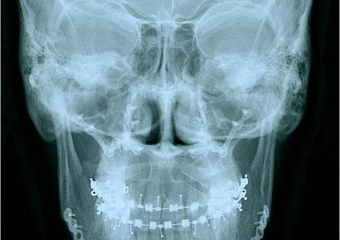

Telerradiografia frontal inicial - Clínica Cliniface

Telerradiografia frontal inicial

Telerradiografia frontal após a cirurgia - Clínica Cliniface

Telerradiografia frontal após a cirurgia